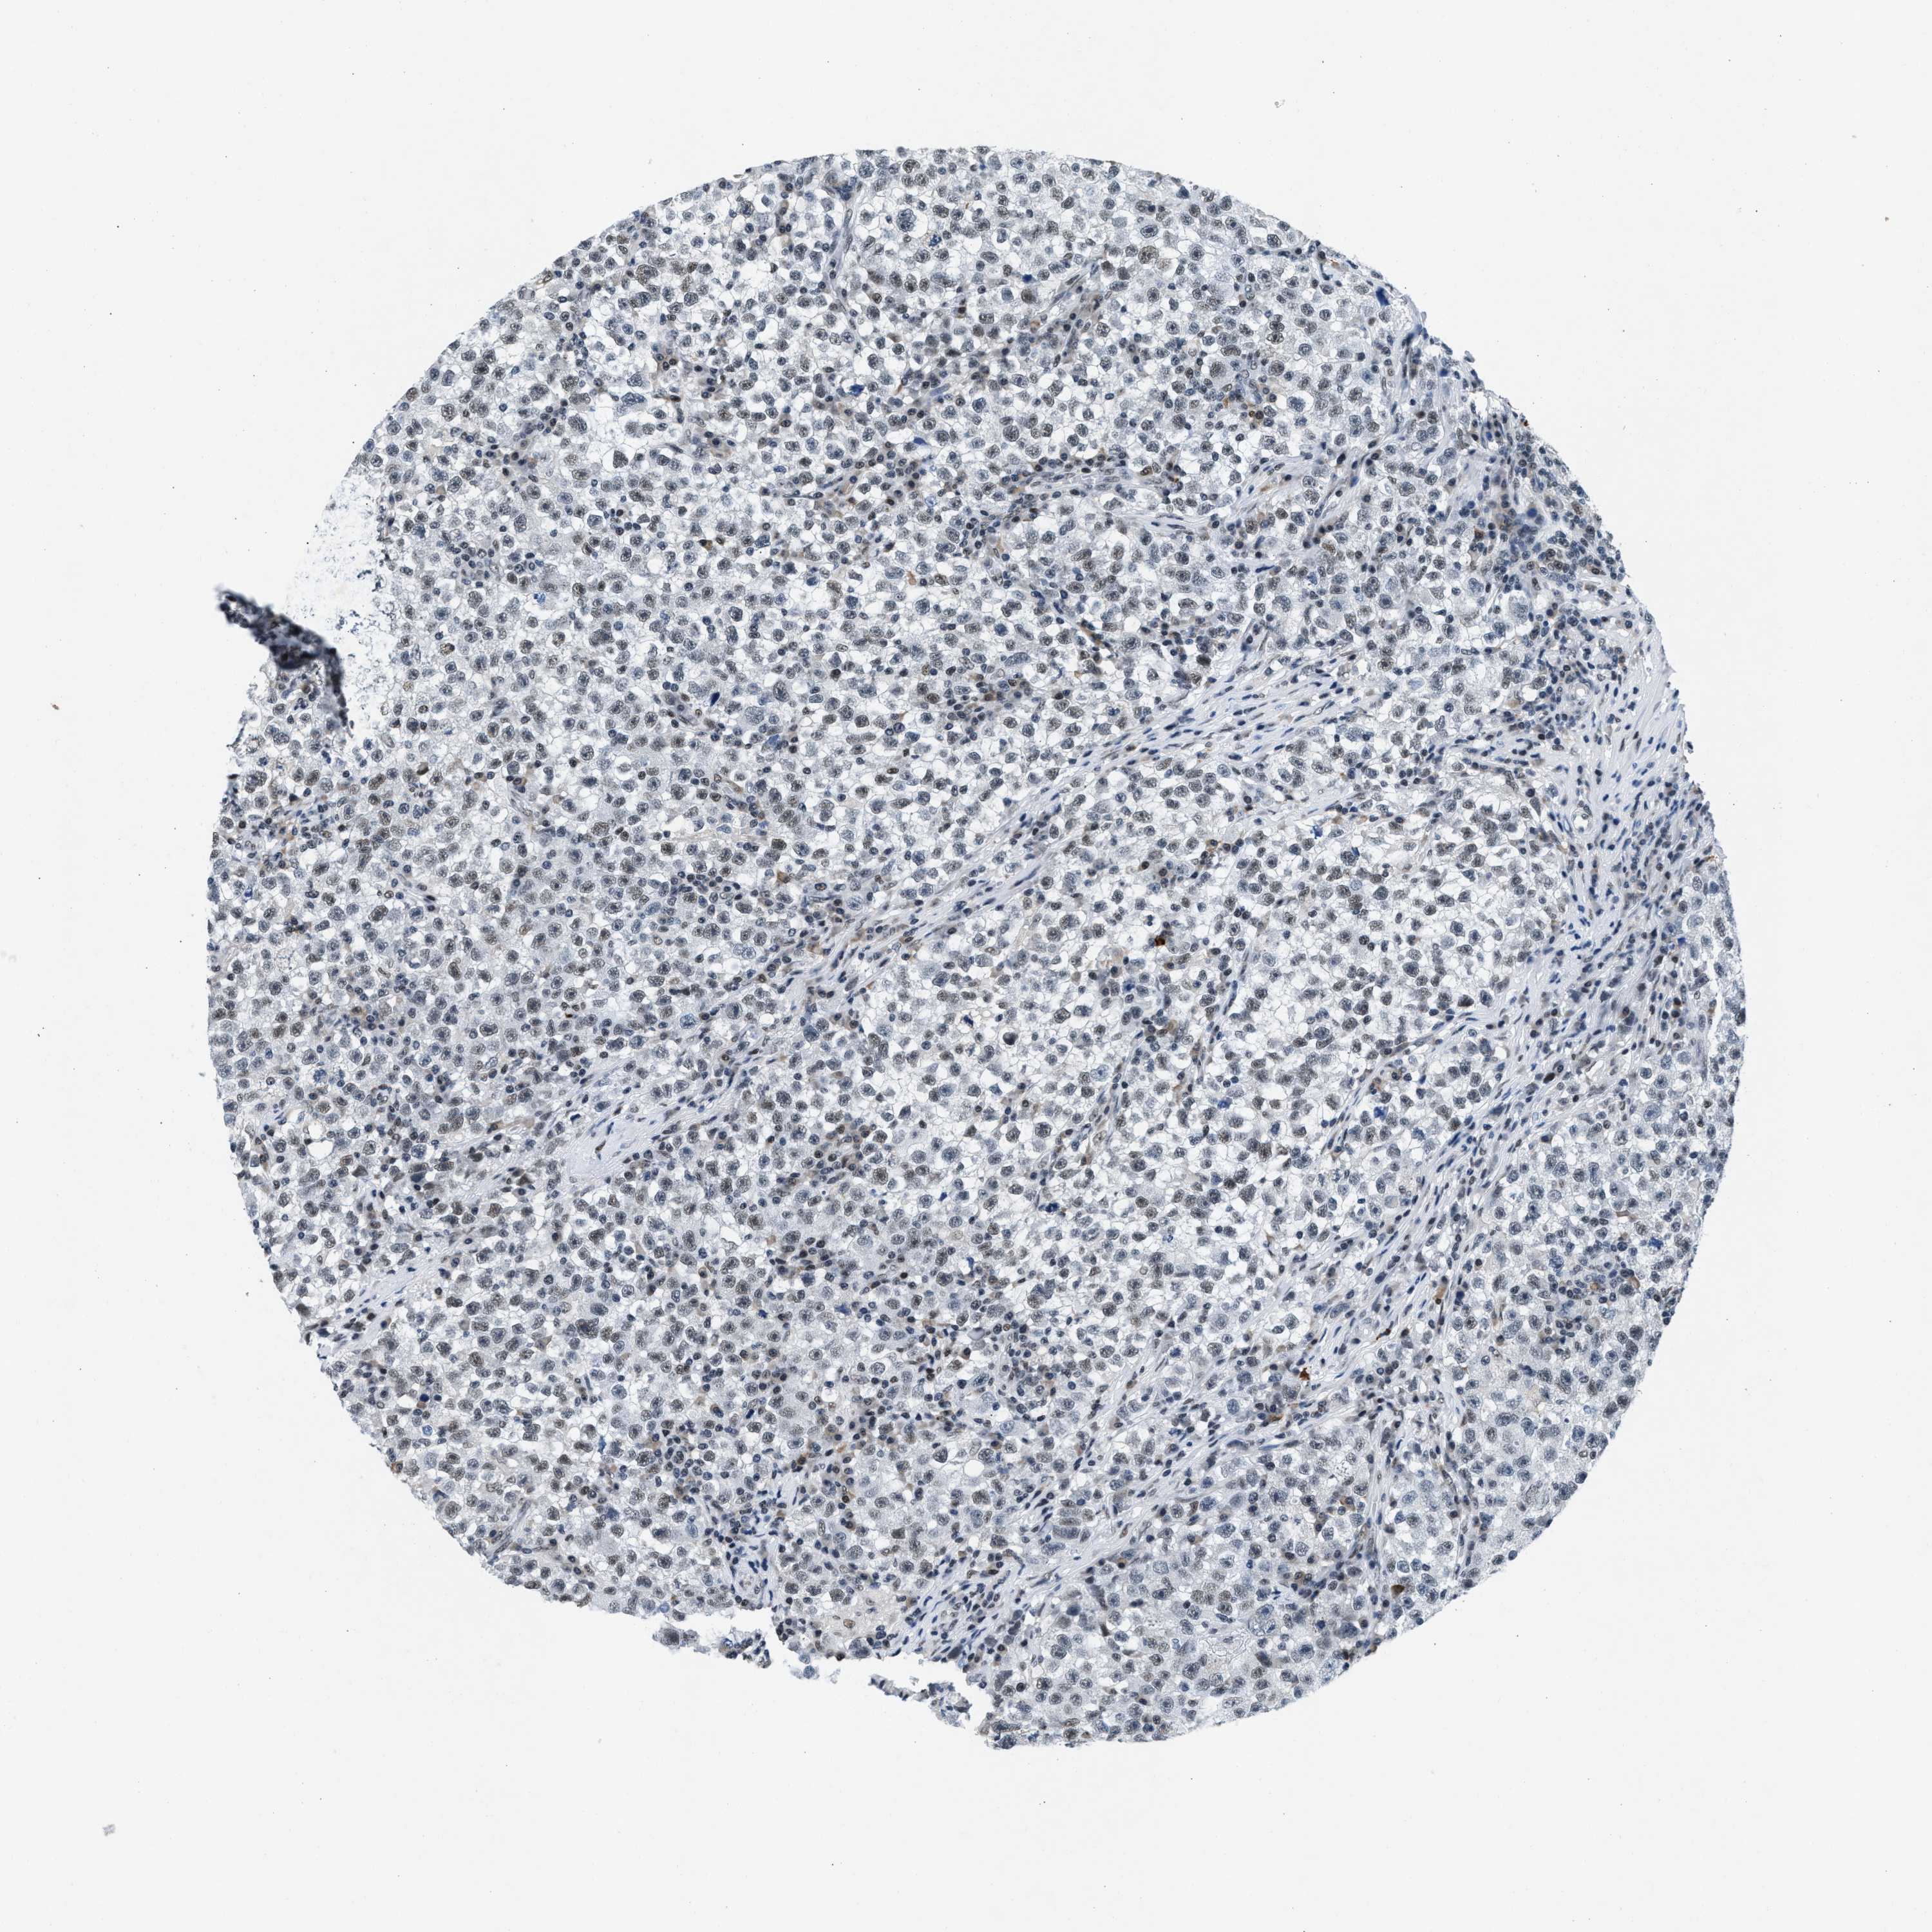

TESTIS CANCER - Protein expressioni

A mouse-over function shows sample information and annotation data. Click on an image to view it in a full screen mode. Samples can be filtered based on level of antibody staining by selecting one or several of the following categories: high, medium, low and not detected. The assay and annotation is described here.

Note that samples used for immunohistochemistry by the Human Protein Atlas do not correspond to samples in the TCGA dataset.

Antibody stainingi

Antibody staining in the annotated cell types in the current human tissue is reported as not detected, low, medium, or high, based on conventional immunohistochemistry profiling in selected tissues. This score is based on the combination of the staining intensity and fraction of stained cells.

Each image is clickable and will lead to virtual microscopy that enables deeper exploration of all samples and also displays staining intensity scores, fraction scores and subcellular localization as well as patient and tissue information for each sample.

Antibody HPA022134

Carcinoma, Embryonal, NOS

Seminoma, NOS